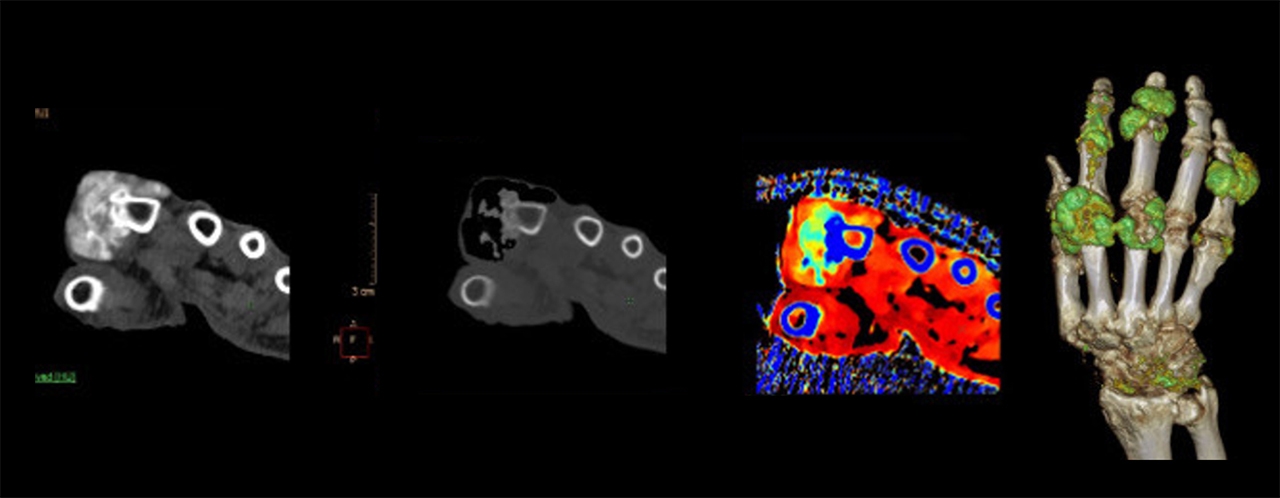

ตรวจนิ่วและเกาต์ได้ละเอียดยิ่งขึ้น ด้วยความสามารถในการแยกแยะองค์ประกอบทางเคมีในร่างกาย เช่น กรดยูริก ทำให้แพทย์สามารถระบุชนิดของนิ่วในร่างกายผู้ป่วยได้อย่างแม่นยำ นำไปสู่วิธีการรักษาที่มีประสิทธิภาพสูงสุด สำหรับผู้ป่วยเกาต์ เครื่องนี้ไม่เพียงแค่ช่วยในการวินิจฉัยโรค แต่ยังสามารถวัดปริมาตรรอยโรคในข้อและสร้างเป็นภาพ 3D ให้แพทย์ตรวจสอบได้ในคราวเดียว

(ซ้าย: ภาพ CT ทั่วไป / ภาพที่ 2-4 จากซ้าย: ภาพ Spectral CT)